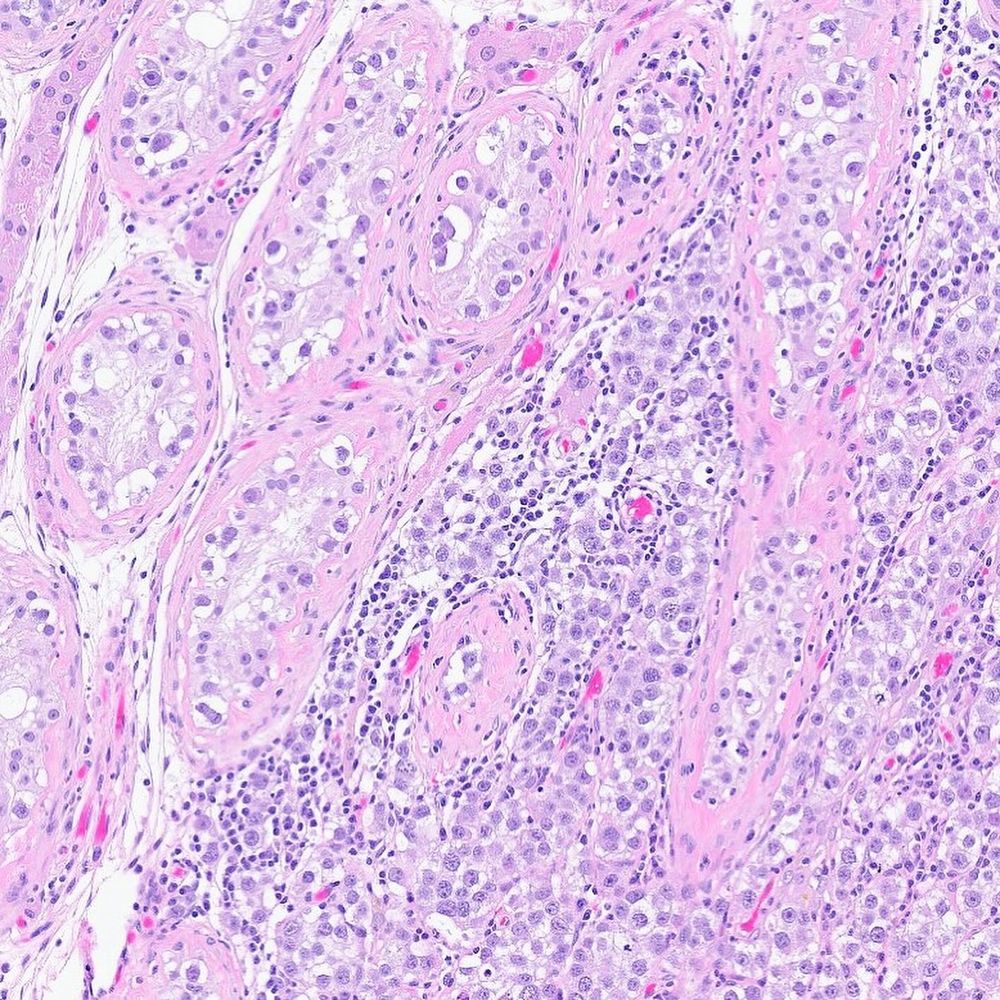

#slidearchiveseries seminoma with brisk lymphocytes, rete testis invasion, and GCNIS—classic 'fried egg' 🍳 appearance with a dash of pepper #gupath #testistumor #pathoutpic